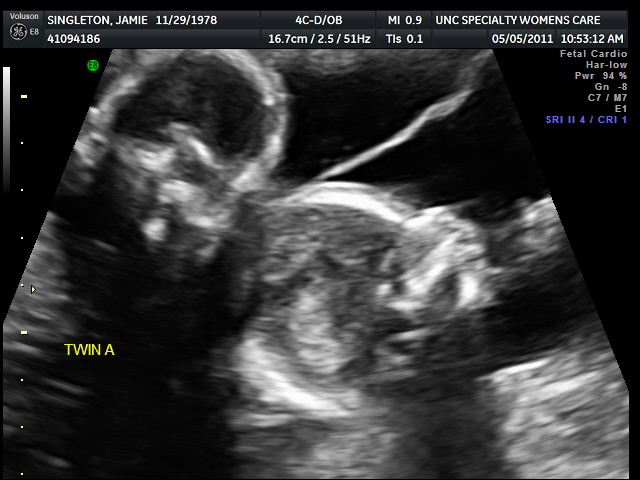

Twin A- looking down to the left (the thin line in the picture coming out from behind Twin A is the membrane that is between Twin A and Twin B seperating them).

I think this picture is self explanatory...